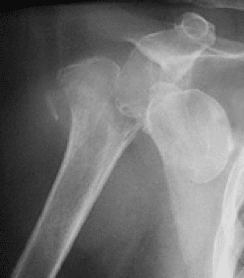

Arthrose is een proces van progressieve afbraak van kraakbeen.

Kraakbeen is een dunne, gladde en elastische structuur waarmee het gewricht bedekt wordt. Hierdoor kan een gewricht vlot en pijnloos bewegen.

Bij progressieve aantasting van dit kraakbeen onstaan er fissuren, afbrokkelingen en onregelmatigheden in deze structuur. Dit heeft een pijnlijke en stijf gewricht tot gevolg. In een verder stadium kunnen ook de omliggende pezen van de rotator cuff aangetast worden met nog meer functieverlies tot gevolg.

schouder arthrose

Indien de pijn of het functieverlies te ernstig zijn kan een schouderprothese een oplossing bieden.